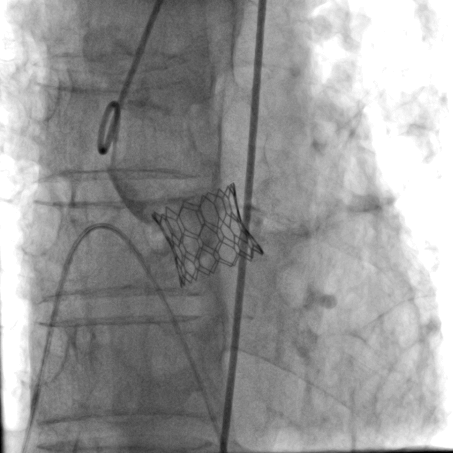

经详尽影像学重建、评估及病例讨论,决定选择经右侧股动脉为主入路,跨瓣成功后先以23#球囊预扩张满意,后植入25# Renatus球扩式介入主动脉瓣,再以24#球囊后扩。手术耗时约1小时,患者全程生命体征平稳,出血极少。介入主动脉瓣植入位置理想,功能表现出色,造影及TEE观察仅轻微瓣周漏,无中央性反流,主动脉瓣峰值流速及平均跨瓣压差分别降至2.3m/s和8mmHg,未发生传导阻滞和冠脉异常。

瓣膜释放 主动脉根部造影